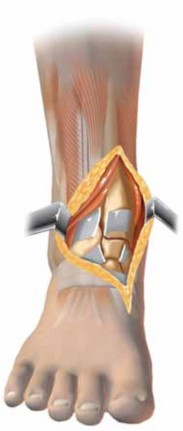

When the posterolateral approach is used, the patient is best positioned prone (or lateral) to allow the surgeon comfortable access to the posterior leg. Approach

39.

Although historically a single “utilitarian” approach was popular in the reconstruction of the tibial plafond, a variety of surgical approaches are currently used to treat these fractures ( FIG 6).

1.

In principle, less dissection and soft tissue retraction, as well as optimal implant placement, should be possible using more direct approaches.

Anterior tibial artery and vein Extensor hallucis longus Extensor digitorum communis Anterolateral approach Deep peroneal n. Tibialis anterior tendon Anteromedial approach Tibia Fibula Peroneus longus m. Peroneus brevis m. Posterolateral approach Sural n. Sural v. Saphenous v. Posteromedial approach Posterior tibial artery and vein Tibial n. Flexor hallucis longus m. Achilles tendon ### FIG 6 • Approaches to the tibial plafond are probably best tailored to match the injury pattern. More than 90% of plafond fractures are well approached anteriorly (anteromedially or anterolaterally), but other approaches are sometimes useful.